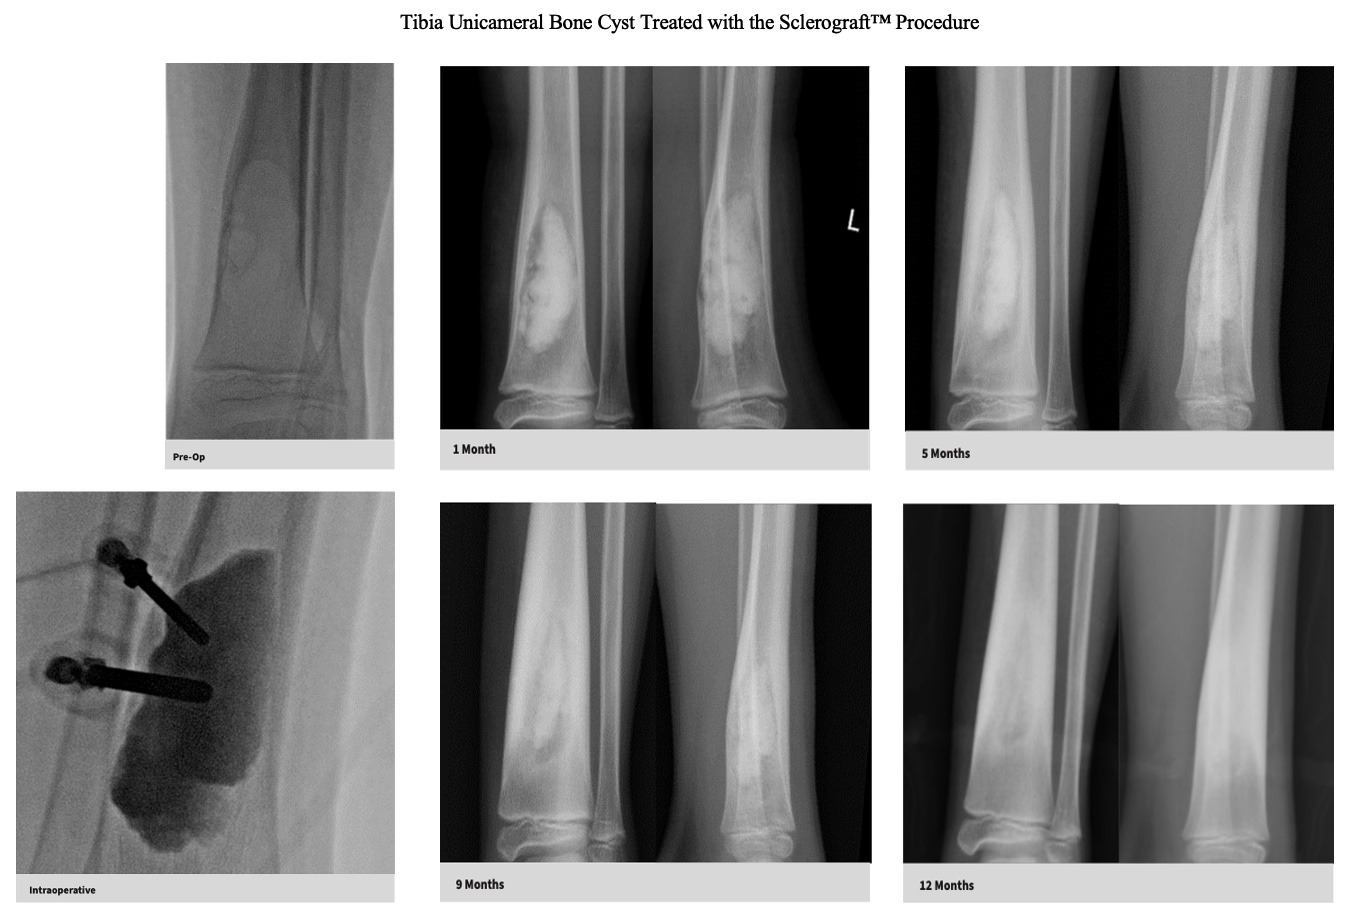

Utilizing needles, chemical sclerosis destroys the cyst wall and regenerative bone graft is injected via the needles to expedite bone healing.

The doctor uses imaging guidance (like X-ray or ultrasound) to guide needles into the cyst.

Chemical sclerosis using chemicals like doxycycline are washed through the cyst to kill the cyst wall lining

Regenerative bone graft is then injected through the needles and the needles are removed. The bone graft is temporary and is eventually reabsorbed by the body.

Quick recovery and bone formation seen between 6 weeks to 3 months

Proven success in both UBCs and ABCs

Bone thickening begins to occur after approximately 6 weeks, so if you child is in a sling or uses crutches, that will be continued until the first x-ray is obtained.

Follow-up imaging is usually obtained at 6 weeks, 3 months, 6 months, 12 months and annually for at least 3 years.

The decision to return to normal physical activity is driven by how well the bone has healed based on the follow-up x-rays.

The long term follow-up with x-rays is critical because of the possibility of bone cyst recurrence. Generally, if a recurrence occurs, it tends to be noticeable by the 6 month mark

Gallery

Explore our educational resources and images